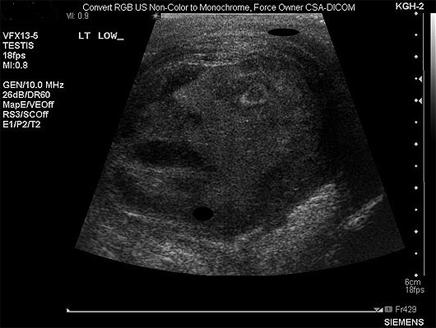

انتشر خبرعن طبيب لبناني الأصل، ناشط في كندا بعلاج أمراض

المسالك البولية وسرطان الخصية وجيرانها، وعن مريضه

الذي جاءه شاكياً من ورم ظهر في الخصية مع بعض الألم، فالتقط لها صورة بالأشعة، وبدلاً من أن يرى الطبيب ما كان يبحث عنه في الصورة، رأى ما أصابه بالدهشة.

استغرب الدكتور ناجي توما أن ما ظهر في الصورة هو "وجه بشري" كامل التقاسيم والملامح، حتى والتعبيرات التي بدت على سمات الوجه الذي بدا وكأنه ينظر بعينيه الى أعلى، واستغرب الدكتور توما أكثر حين أخبروه بأن الوجه شبيه الى حد ما بإله الخصوبة لدى الفراعنة، المعروف باسم "مين" للأثريين.

وكان الفراعنة يعرفون "مين" بأنه يرأف بالمصابين بالعقم من النساء أو الرجال، أو يشفي مرضى العجز الجنسي، فأقاموا له التماثيل بلون غامق شبيه بالطين وطمي النيل، أي تقريبا باللون الذي ظهر فيه الوجه بالصورة التي وصل صداها سريعا الى وسائل الإعلام،